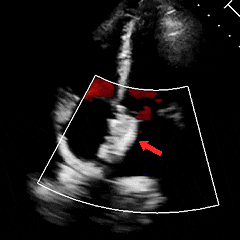

经胸右心声学造影:经左肘静脉注入震荡生理盐水(8mL生理盐水+1mL回抽静脉血+1mL空气经震荡制成),上腔、右房依次显影,造影剂完全充盈右心后,平静呼吸时,左房内即可探及微泡回声,约20-30个/切面/帧;瓦氏呼吸释放即刻,左房内探及微泡回声,不可计数。

术前瓦氏动作后经胸右心声学造影(大量)